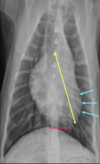

Which structures are outlined in this image?

A

light blue: ascending aorta

mint: main pulmonary artery